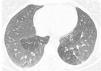

A 61-year-old man, non-smoker, with a history of ulcerative colitis, who had been receiving sulfasalazine treatment for more than 3 years, consulted in January 2012 with a 6-month history of dry cough and progressive dyspnea. Spirometry showed severe airflow obstruction (FEV1=890ml [30%]; FVC=1670ml [44%]; FEV1/FVC=[53%]). High-resolution computed tomography (HRCT) revealed bilateral pulmonary opacities, predominantly in the upper lung regions. Clinical laboratory tests showed eosinophilia in blood and in bronchoalveolar lavage fluid (7.6g/l and 80%, respectively). The patient was diagnosed with eosinophilic pneumonia; sulfasalazine was switched to 40mg prednisone once a day, resulting in clinical and functional improvement. The patient was not followed up. In September 2013, he presented again with a 5-month history of dry cough and progressive dyspnea. He had discontinued prednisone prematurely, and against our advice, had started taking sulfasalazine again. Spirometry showed an obstructive ventilatory defect (FEV1=905ml [31% predicted]; FVC=1300ml [34% predicted]; FEV1/FVC=[69% predicted]). Arterial blood gases revealed hypoxemia, HRCT found bilateral areas of mosaic attenuation (Fig. 1), and clinical laboratory results showed 1.9g/l eosinophils in blood. Fiberoptic bronchoscopy showed hyperemia throughout the tracheobronchial mucosa, endobronchial biopsy found prominent eosinophil inflammation, and 32% eosinophils were seen on the bronchoalveolar lavage (BAL) leukocyte formula. Sulfasalazine was withdrawn, and the patient began treatment for HOB with 40mg prednisone once a day and nebulized bronchodilators and corticosteroids, producing notable clinical and functional improvement. In November 2013, the patient's FEV1 was 2900ml (114%) and FVC 3810 (105%). We recommended a gradual reduction over the course of several weeks of the initial dose of corticosteroids to the minimum maintenance dose for normal lung function and control symptoms. The patient also received formoterol/budesonide.